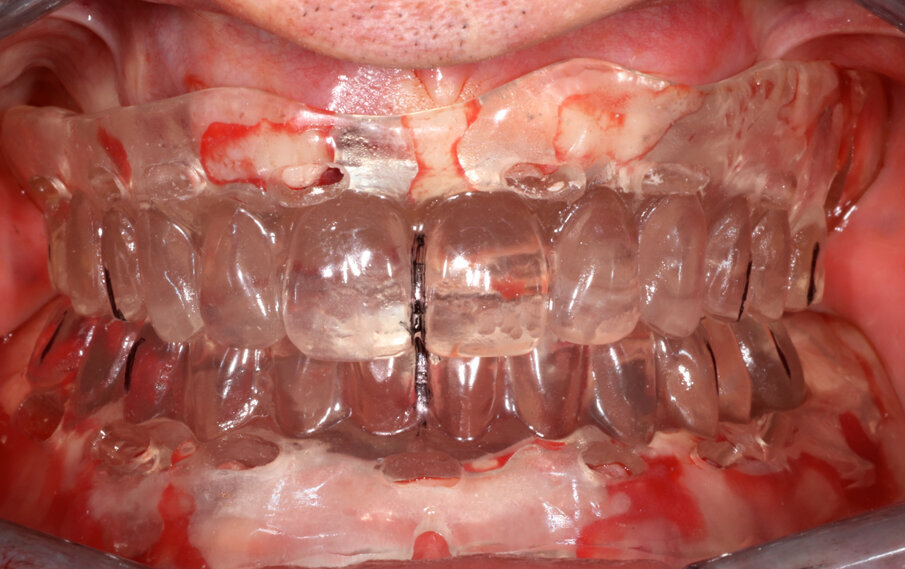

Al momento dell’intervento, eseguito in sedazione intravenosa e anestesia locale (Scandonest 2%, epynephrin 1:100.000, Septodont), si procede alla bonifica di tutti gli elementi dentali e degli impianti considerati non recuperabili (Fig. 3) e, successivamente, alla prova delle mascherine protesiche preparate dal laboratorio per verificare l’occlusione e la congruità con la ceratura diagnostica, eseguita in precedenza (Fig. 4). A questo punto, la mascherina superiore viene fissata ai due impianti residui in zona 14 e 27 come punto di riferimento per l’intervento a livello mandibolare.

Fig. 4_Mascherine protesiche in posizione per il controllo dell’occlusione e della ceratura diagnostica eseguita.

Completata la sutura del lembo, la fase della presa dell’impronta è stata eseguita seguendo il medesimo protocollo, già descritto in precedenza. Per eseguire l’incollaggio delle cappette protesiche sulla mascherina superiore, è stata riposizionata la mascherina inferiore, una volta completato lo sviluppo del modello in gesso inferiore. Si è proceduto quindi, una volta di più, al controllo della posizione della mascherina prima di procedere all’incollaggio delle cappette protesiche superiori. Dopo circa due ore dal termine della fase chirurgica, completata la costruzione in laboratorio del manufatto, le protesi provvisorie sono state consegnate e avvitate sugli impianti, previo accurato controllo e bilanciamento dei contatti occlusali (Fig. 7).

Fig. 7_Controllo dell’occlusione delle protesi provvisorie appena consegnate al paziente.